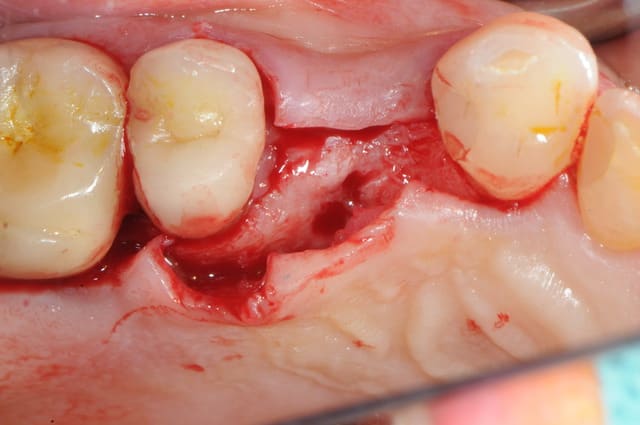

pour débuter ce post je propose un petit cas avec une ROG un comblement alvéolaire et un lambeau pédiculé pour fermer le site d'extraction.

au début incision supra crestal puis lambeau muco-périosté.

avec une simple lame 11 qui tranche le long de gencive palatine. évidemment c'est le plus dure à faire pour éviter de transpercer ou d'avoir d'un coté ou de l'autre une épaisseur trop faible.

Au maxillaire je procède de la même manière: extraction, curetage, comblement et greffon conjonctif pédiculé. Le punch épithélio-conjonctif ne m'a pas vraiment donné jusqu'à présent de meilleurs résultats que le conjonctif pédiculé et en post-op je trouve que c'est plus douloureux pour le patient.